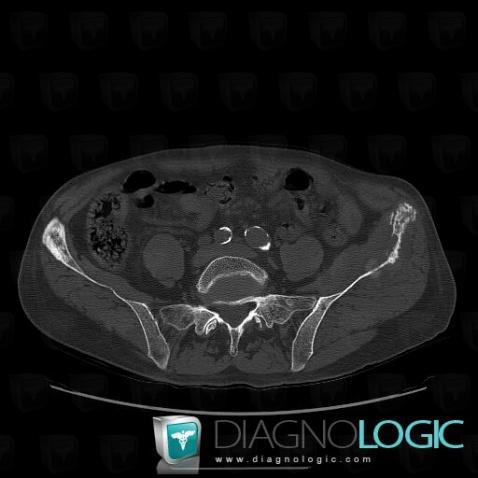

Metastasis, Ilium, CT

Here is the specific information in the key image above:

- Diagnosis Metastasis, Location(s) Ilium, with gamuts Cortical thickening